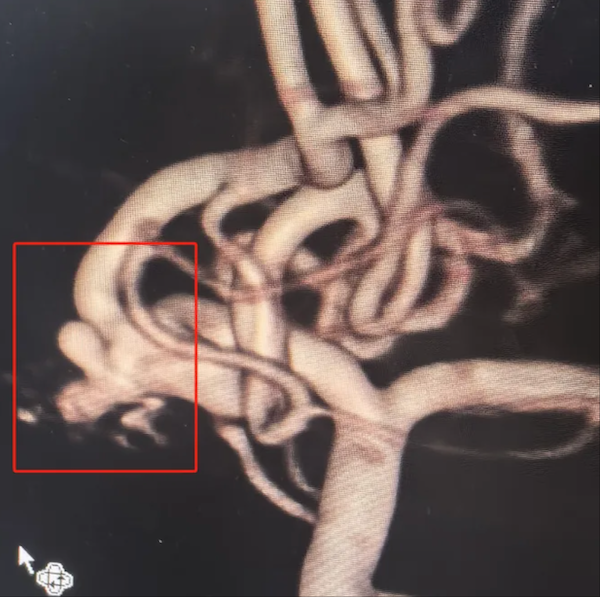

上图是一位复杂脑动脉瘤患者的术后影像